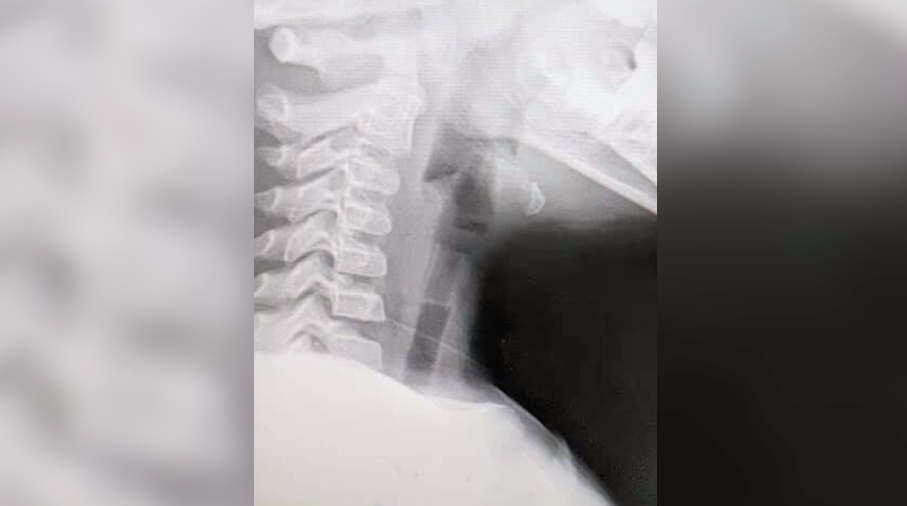

หนูน้อยวัย 4 ขวบ ถูกครูพาส่งโรงพยาบาลยะลาหลังกลืนนกหวีดลงคอ จนหายใจออกมาจะได้ยินเสียงหวีดๆ แพทย์หญิงกฤษณพร จิรวรากุล แพทย์องค์กรแพทย์ หู ตา คอ จมูก โรงพยาบาลยะลาบอกว่า ยังโชคดีที่นกหวีดเป่าลมมีรู ทำให้มีช่องลมให้หายใจเข้าออกได้ตามปกติ เพราะไม่ได้อุดตันร้อยเปอร์เซ็นต์ เพียงแต่จะมีเสียงดังเท่านั้น แต่หากสิ่งของที่หลุดลงไปไม่มีท่อหรือช่องลม ก็จะทำให้เด็กขาดอากาศหายใจอาจถึงขั้นเสียชีวิตได้ เมื่อมาถึงโรงพยาบาลได้เอกซเรย์ เมื่อรู้ตำแหน่งได้วางยางสลบ เปิดบริเวณกล่องเสียงแล้วคีบออกมาได้อย่างปลอดภัยใช้เวลาประมาณ 15-20 นาที จากการสอบถามครูที่อยู่ในเหตุการณ์เล่าให้หมอฟังว่า ที่รู้เพราะเด็กมีอาการไออย่างรุนแรง จึงสงสัยว่าสำลักสิ่งแปลกปลอมเข้าไปโดยนกหวีดเมื่อตกผ่านสายเสียงแล้วได้หล่นไปในหลอดลม และค้างที่หลอดลมส่วนต้น ทำให้เมื่อเด็กหายใจเข้า-ออก จึงมีเสียงนกหวีด ดังออกมา